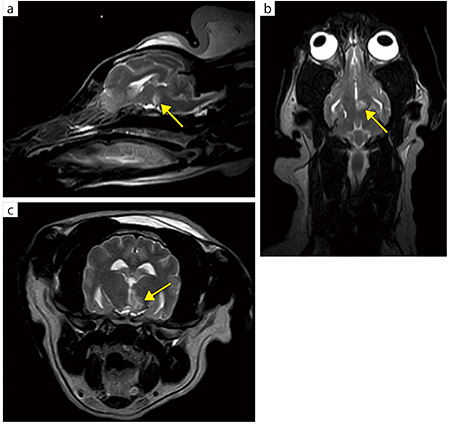

■症例5:イヌ,頭部肉芽腫性脳炎

a:膝コイル,T2WI,SAG,FOV:220mm,TR/TE:4500/100,スライス厚:3mm,マトリックス:256×180,scan time:4:08

b:膝コイル,T2WI,COR,FOV:220mm,TR/TE:4500/100,スライス厚:3mm,マトリックス:256×180,scan time:4:08

c:膝コイル,T2WI,AXI,FOV:150mm,TR/TE:4600/100,スライス厚:3mm,マトリックス:224×192,scan time:7:27